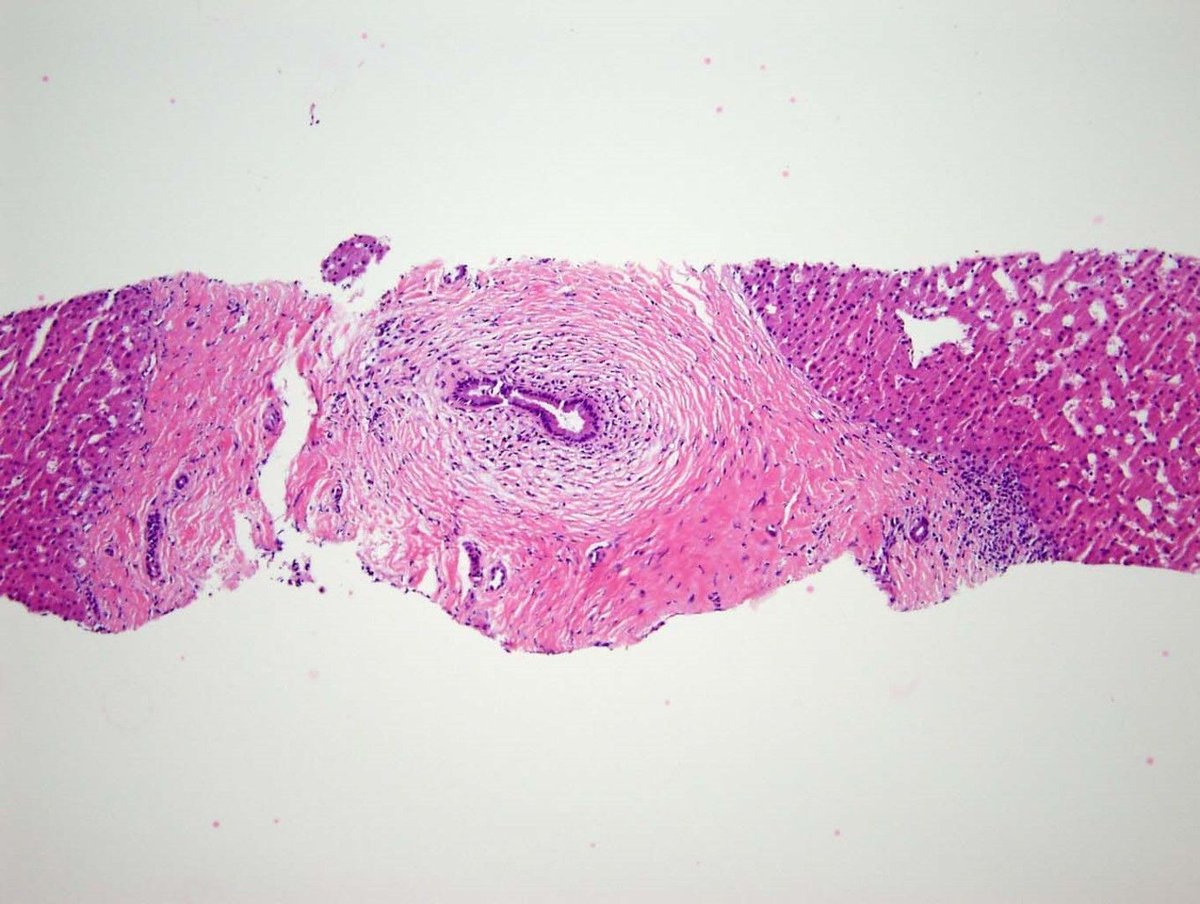

#Pathresidents: Let’s take a look at two biopsy cores (from the same patient) and decide what to call them.

Take a look at both cases (“A” in this post, “B” in reply). Cast your vote. Then, read on for some teaching points geared towards trainees and general fans of #GUPath.